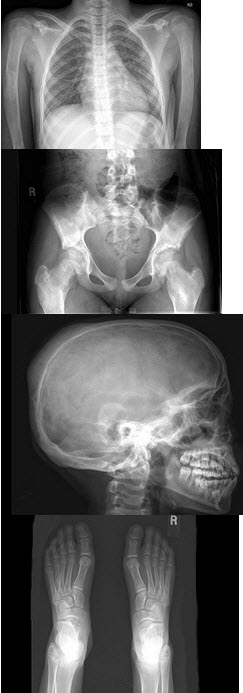

A.骨端骨质疏松

B.周围肌肉萎缩

C.骨质破坏先从非承重关节开始

19、单项选择题

男,5岁,髋部疼痛乏力伴跛行5个月,结合图像,最可能的诊断是()

C.白细胞

D.网状细胞

46、单项选择题

女,根据其正常骨盆影像图像,判断其最可能的年龄()

A.69岁左右

B.59岁左右

C.49岁左右

D.19岁左右

E.39岁左右

男,根据其正常骨盆影像图像,判断其最可能的年龄()

A.5岁左右

B.10岁左右

C.15左右

D.20岁左右

E.25岁左右